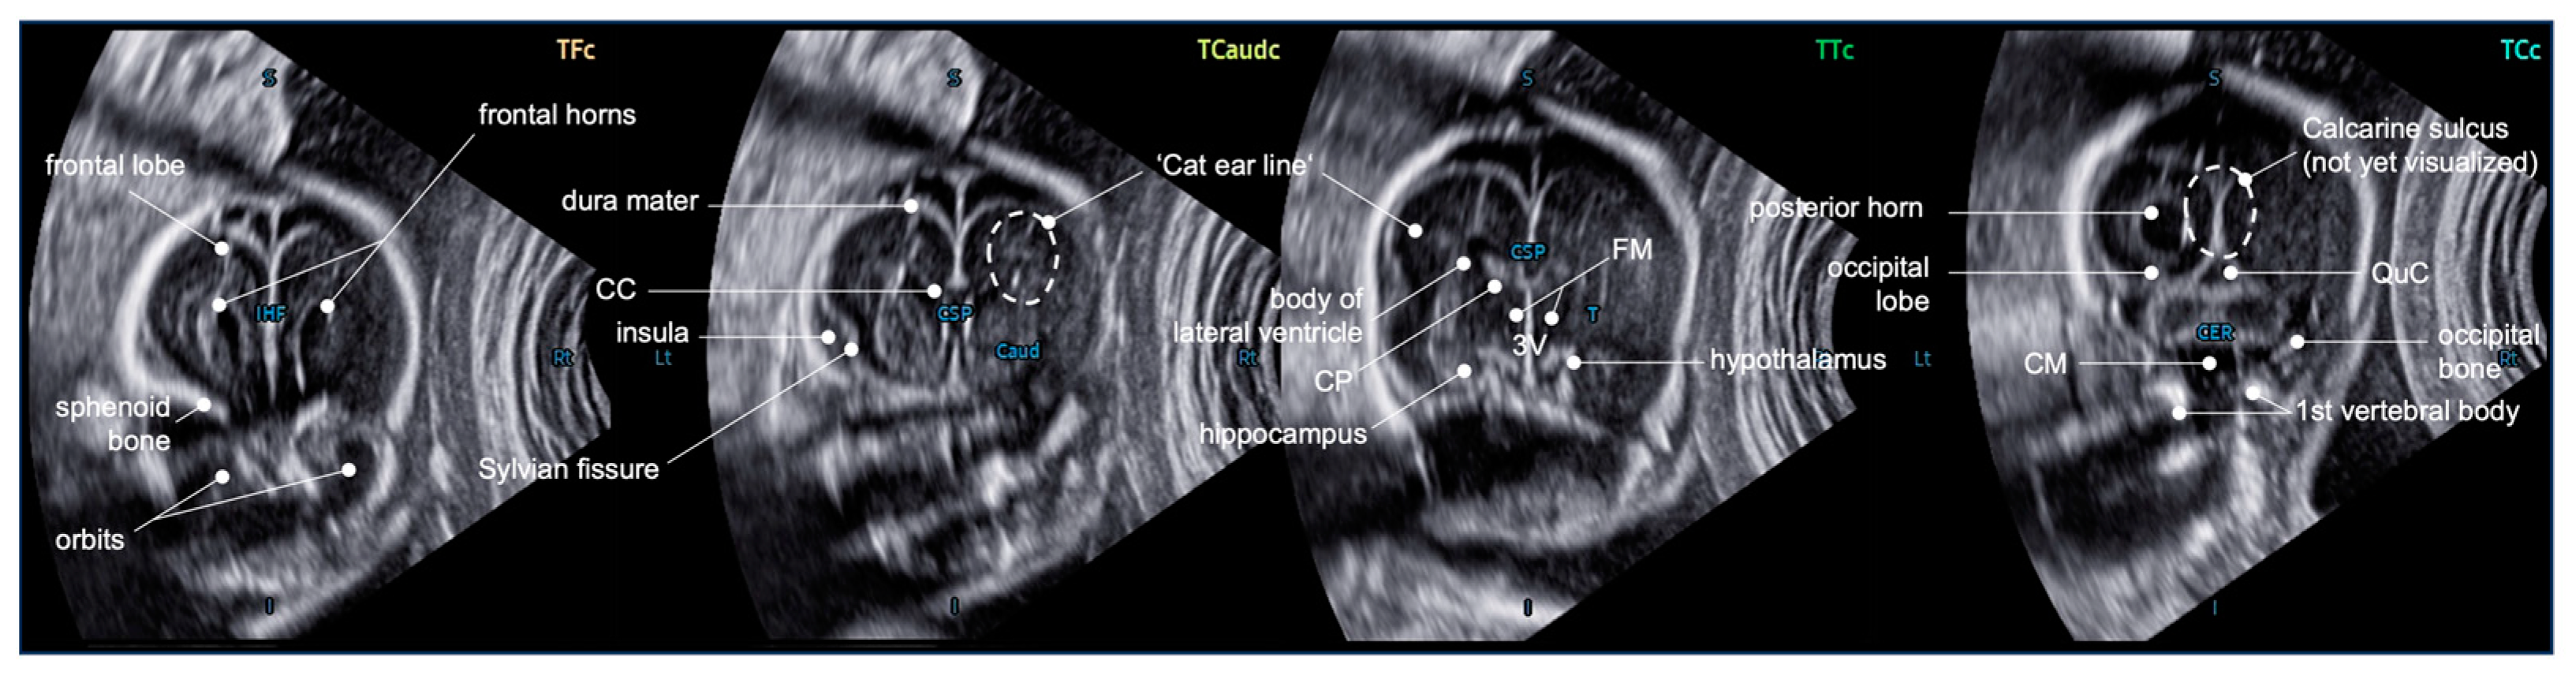

2.2. SonoCNS™

2.3. 5DCNS+™

4.3. Additional Value of the Coronal Planes